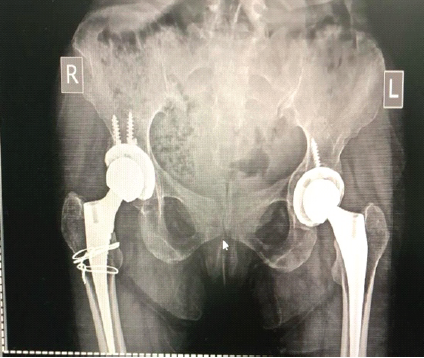

A post-operative image after both hip replacements displays well-aligned bilateral prostheses with no evidence of loosening or malposition (Fig. 6). Perioperative care included addressing anemia, administering calcium and Vitamin D supplements, implementing thromboprophylaxis, and starting early rehabilitation.

Figure 6: Post-operative X-ray showing both hips with well-positioned prostheses (January 14, 2025).